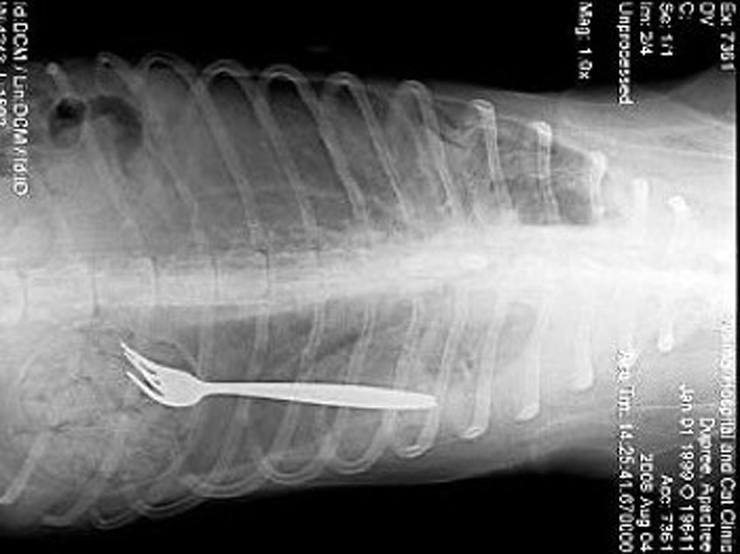

Вилка

На снимке собака из штата Северная Каролина, США, которая проглотила вилку.